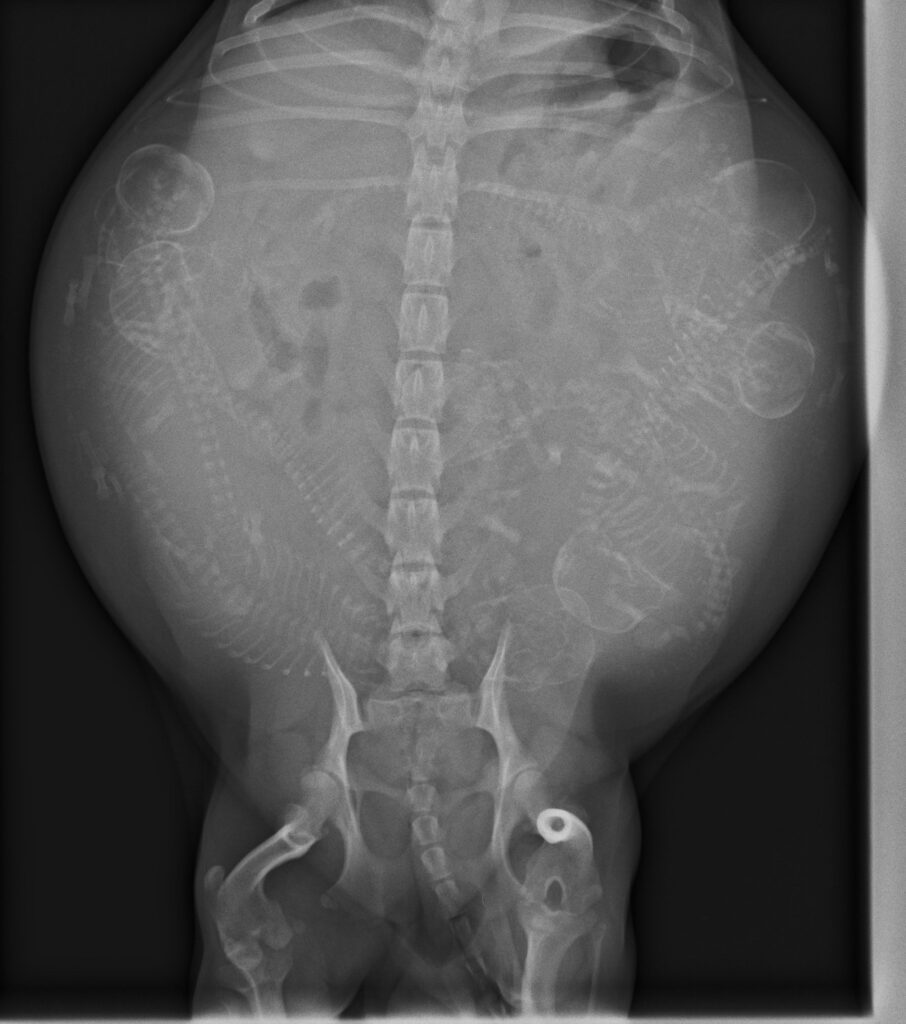

レントゲン検査は胎児の骨を投影することで、胎児の頭数を知る検査として用いられます。

そのため、頭蓋骨がはっきりとみえる時期(犬では50日ごろ、猫では40日ごろ)に検査を実施するのが望ましいとされています。